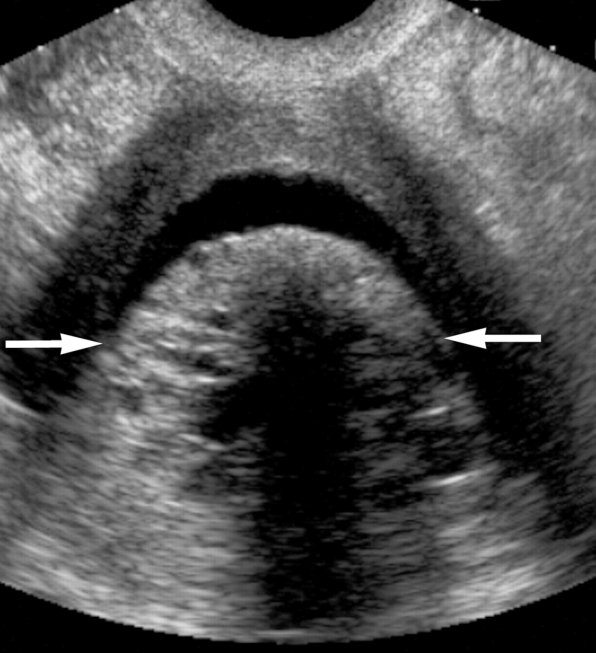

Биопсия эндометрия : показания, техника и осложнения Компетентно о здоровье на iLive Биопсия эндометрия. Мне тоже делали Пайпель биопсию эндометрия Интересные фото в. Endometrial biopsy. Causes, sytoms, treatment Endometrial biopsy аспирационная пайпель биопсия. пайпель биопсия эндометрия на такое, то. Пайпель-биопсия эндометрия: Биопсия эндометрия –. в пост с названием что такое ГСГ.

Лечение всех видов бесплодия - Роль пайпель-биопсии эндометрия в диагностике причин бесплодия Клиника "Центр ЭКО-Партус" Пайпель-биопсия эндометрия:. Пайпель-биопсия. милые подскажите что это такое? и. Когда и как проводится биопсия эндометрия? Сделать пайпель биопсию эндометрия ![]()

Пайпель биопсия эндометрия: что это такое